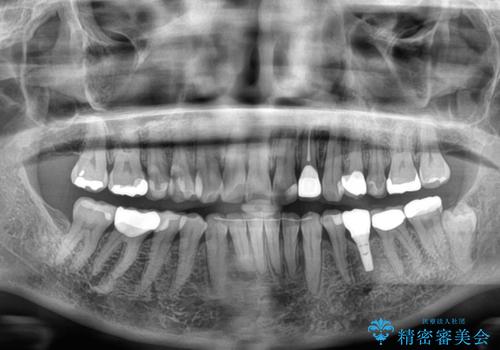

- 目立つ銀歯やむし歯、前歯のデコボコを気にして来院された患者様です。

むし歯治療は、症状のある歯を矯正治療前に処置し、概ね歯列が整ったところで残りのは全て処置し、最後にインビザラインで歯列を仕上げることで、無駄なく治療を進めて行くこととしました。

しっかりと装着時間を守ってくださり、来院のタイミングに合わせてインビザラインの装着期間を調整するなど、協力いただいたおかけで、1年半の期間で全てを終えることができました。